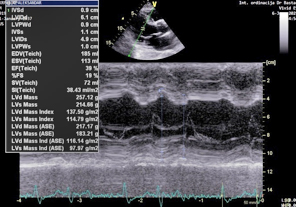

EHOKARDIOGRAFIJA: U nalazu dominira dilatacija leve

komore, normalne debljine zidova leve komore , bez hipertrofije

miokarda i sa sniženom globalnom sistolnom funkcijom: ejekciona

frakcija (EF) leve komore je 39% u M modu (Teicholtz) (Slika 2), a

po Simpsonu 35% i 39%, a biplejn 37% (Slika 3,4).

Slika 2. M MOD EHOKARDIOGRAM ejekciona frakcija

EF=39% po Teicholz-u